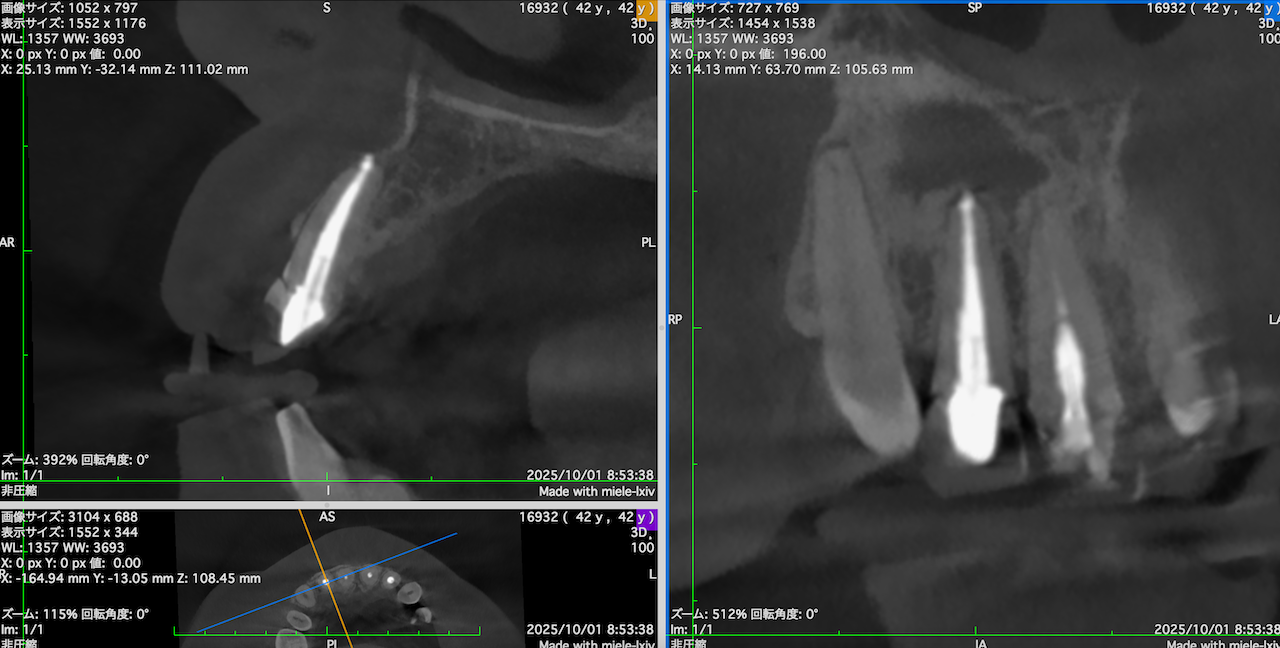

#7,10 Re-RCT 10M recall(2025.10.20)

症状が消失している。

ということは、治癒しているのだろうか?

が、この絵だけで治癒しているかどうか?判断がつくだろうか?

無理だ。。。

そこで、CBCTも撮影した。

#7

#10

これでも判然としかねる。

そこで、

CareStream(日本ではヨシダ社)のCBCTなら以下のようにMPR(Multi-Planar Reconstruction)画面を作成することができる。

それを過去のそれと比較してみた。

↓

このMPR画像からこの患者さんは#7,10ともに外科治療など要らないということがわかるだろう。

無論、検査の結果からそれは必要はないと言えるが、

客観的に不要であるということを患者さんに伝えるにもこの画像機能(MPR画像)は非常に有効である。

ということで今日は、このMPR画像機能について論じてみた。